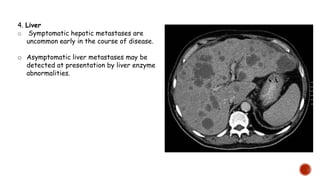

4. Liver

o Symptomatic hepatic metastases are

uncommon early in the course of disease.

o Asymptomatic liver metastases may be

detected at presentation by liver enzyme

abnormalities.